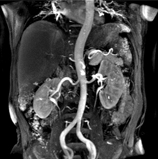

呼吸の動きに合わせて撮影したり、呼吸を止めて撮影したりすることで、腹部の臓器を明瞭に描出することができます。

造影剤を用いて下肢血管を描出することも可能ですが、MRIでは造影剤を用いなくても下肢血管を描出することが可能です。

比較的太い血管の狭窄や塞栓の診断に有用な検査です。